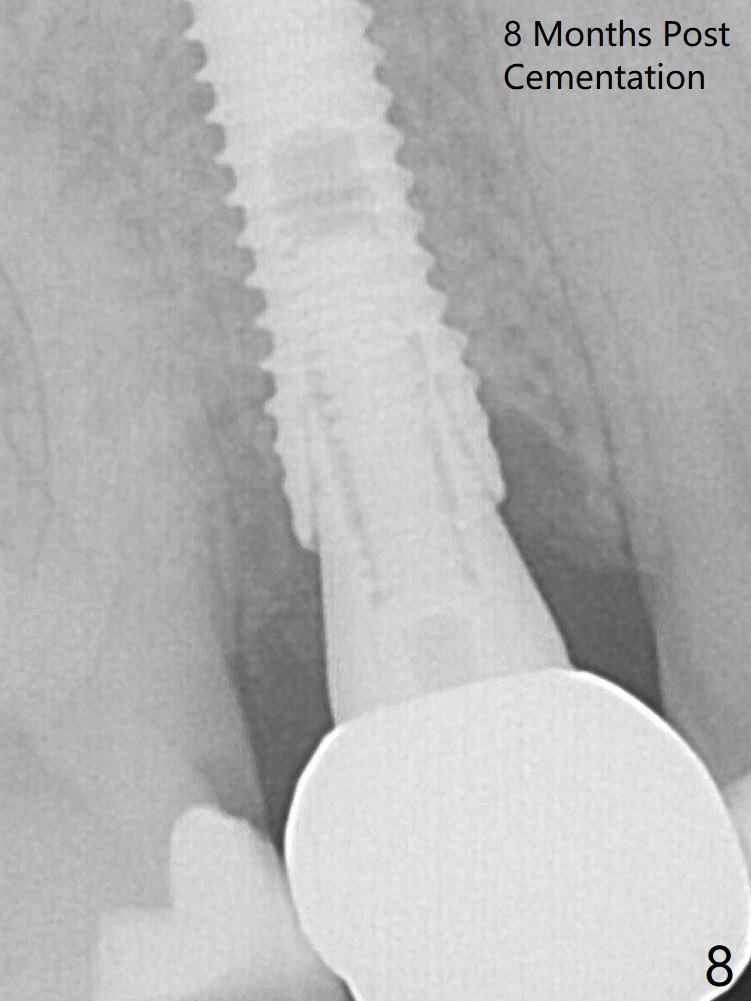

A 3.8x18 mm (definitive) implant is placed with <40 Ncm with the implant plateau apical to the lingual crest (Fig.4 (dashed line: upper border of the buccal defect)).  The buccal plate defect is repaired by Vanilla Graft (Fig.6 *) before and after insertion of a 4.5x4(3) mm abutment.  The buccal plate defect seems to being repaired 4 months postop (Fig.7).  The defect repair is close to completion 8 months post cementation (Fig.8).

In fact there is a small buccal fistula, which is communicated with the underlying implant threads.  It appears that the buccal plate regeneration is incomplete (Fig.9 arrowheads).